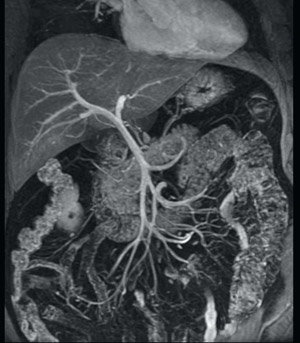

図7 LAVA-FLEXの画像例

体幹部用32チャンネルコイルによるコロナル撮像。造影後,門脈相のボリュームデータからのボリュームリフォメーションによる門脈の描出。大きなFOVでも均一な脂肪抑制を実現。

(画像ご提供:聖隷浜松病院様)